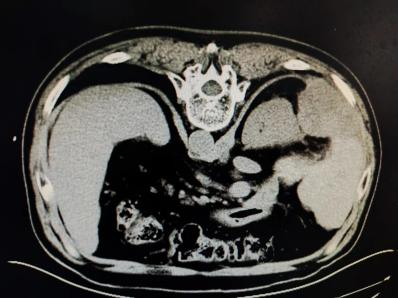

患者张某,以“发现肝恶性肿瘤4年余,右胁部疼痛1月余”为主诉入院,患者4年余前发现肝癌,于当地医院行手术切除,自2019年3月至2023年3月,间断于介入科行介入化疗及栓塞术,病情控制平稳,近1月出现右胁部疼痛,分析上腹部CT影像学可见:肝右后叶及膈肌旁转移瘤,转移瘤紧临右肾及腹膜,上增强CT提示肝转移瘤乏血供。查体可见:右上腹部及脐右侧压痛阳性,腹部无反跳痛,肝区叩击痛阳性。

分析CT影像学资料